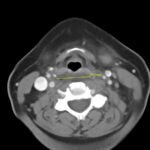

Retropharyngeal abscess (RPA) is an uncommon yet potentially life-threatening condition that is more often seen in young children and may be misdiagnosed in adults presenting with atypical features.1 Retropharyngeal abscess results from spread of antecedent upper respiratory tract infection or traumatic inoculation via foreign body ingestion or medical instrumentation. Clinically, RPA may present with fever, pharyngitis, neck pain, and dysphagia. Diagnosis is often confirmed with imaging studies. We present a case of a 66-year-old female with asthma, hypertension, and gastroesophageal reflux disease (GERD) who presented to the emergency department (ED) for evaluation of neck fullness, shoulder pain, dysphagia, and abdominal pain starting less than 24 hours prior to presentation. Computed tomography (CT) revealed a prevertebral/retropharyngeal fluid collection from the odontoid tip to the C4 vertebral body measuring 5.4 x 1.0 x 3.3 centimeters (cm) in size with associated edema at the left neck base extending into the upper chest, suggestive of retropharyngeal abscess. The patient received intravenous (IV) vancomycin and piperacillin/tazobactam and was transferred to a higher level of care for otolaryngologist evaluation. The patient remained stable without airway compromise while in our department. This case underscores challenges in diagnosing atypical presentations of RPA in adults, emphasizing timely recognition to prevent complications.